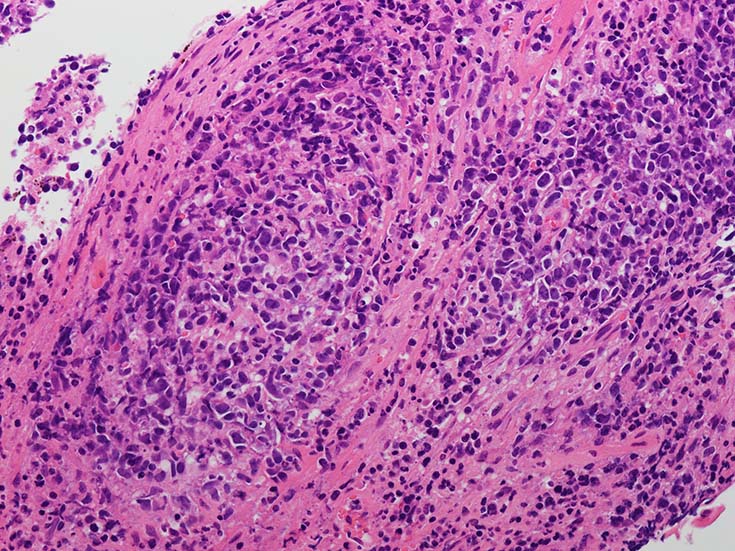

EBUS-GS(ガイドシース併用気管支腔内超音波断層法)による肺生検組織病理所見.

血管周囲性に大型類円形核や不整形核をもつ腫瘍細胞がシート状密に浸潤増殖している. Mitosisが多く認められる.細血管閉塞や破壊の所見がある.

間質にもシート状の腫瘍細胞浸潤がある. 大小 pleomorphicな傾向.(A, B). necrosisが認められる(C). 細気管支上皮直下まで密な浸潤あり, 小型リンパ球が混在している.(D)

血管中心性浸潤. 障害された血管内に血栓が形成されている.CD20陽性細胞がシート状密に浸潤, CD3陽性T細胞が多く混在している. EBER-ISH陽性 EBV感染細胞が多数認められ, >50 hpf, 定義より Grade3となる. 陽性細胞のサイズは大小さまざまであることに注意. Lymphomatoid granulomatosisの病態(WHO5thの診断では EBV-positive diffuse large B-cell lymphomaになる)をとっているが MTX-associated LPDの一型とするべき症例かもしれません.